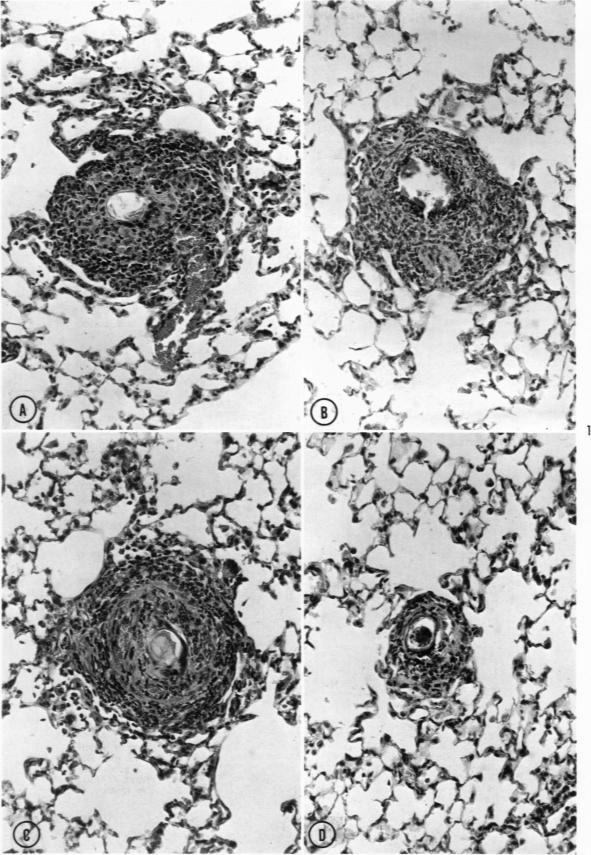

Perrotto J L, Warren K S

Am J Pathol. 1969 Aug;56(2):279-91.